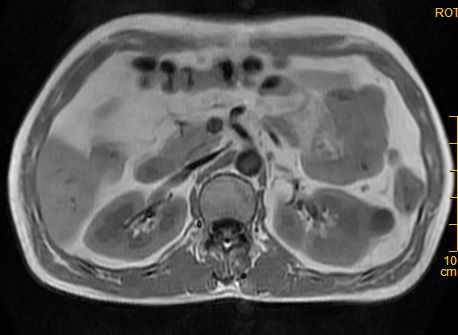

标题: MRI2883:左肾占位性病灶,请大家来会诊!

左肾占位性病灶,请大家来会诊!

考虑多发囊肿融合

肾癌

多囊性肾瘤

考虑 1囊性肾癌 2多囊性肾瘤。

考虑左肾囊性肾癌,多囊性肾瘤待排。

考虑左肾囊性肾癌,多囊性肾瘤待排。建议增强。

左肾癌囊变。

左肾复杂性外生囊肿,错构瘤待排。